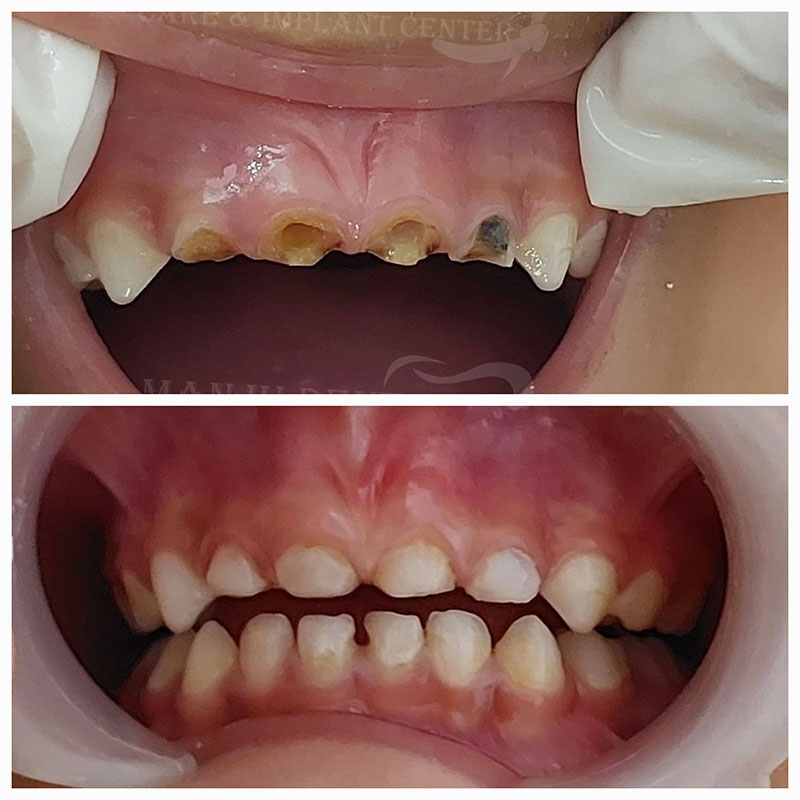

Little Smile Restored With Anterior Composite Build-Up